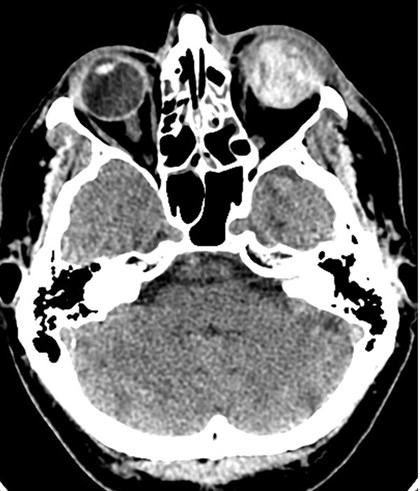

CT scan case three: The left eye is completely disrupted with no internal recognisable features. The globe is protruding forwards due to swelling of the soft tissues within the orbit.